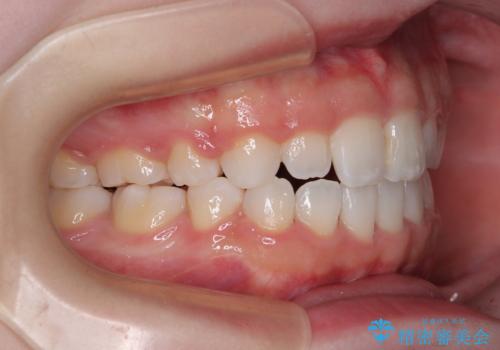

- 前歯が開いて飛び出していることを気にして来院された患者様です。

舌の突出癖により上下前歯は接触できず、更には前方に押し出されて出っ歯になっている状態でした。

上下左右の第一小臼歯4本を抜歯し、ワイヤー装置での抜歯矯正を行っていくのですが、原因である舌の突出癖を改善しないことには治療がうまく進められないため、舌のトレーニングを徹底するよう指導していくこととしました。